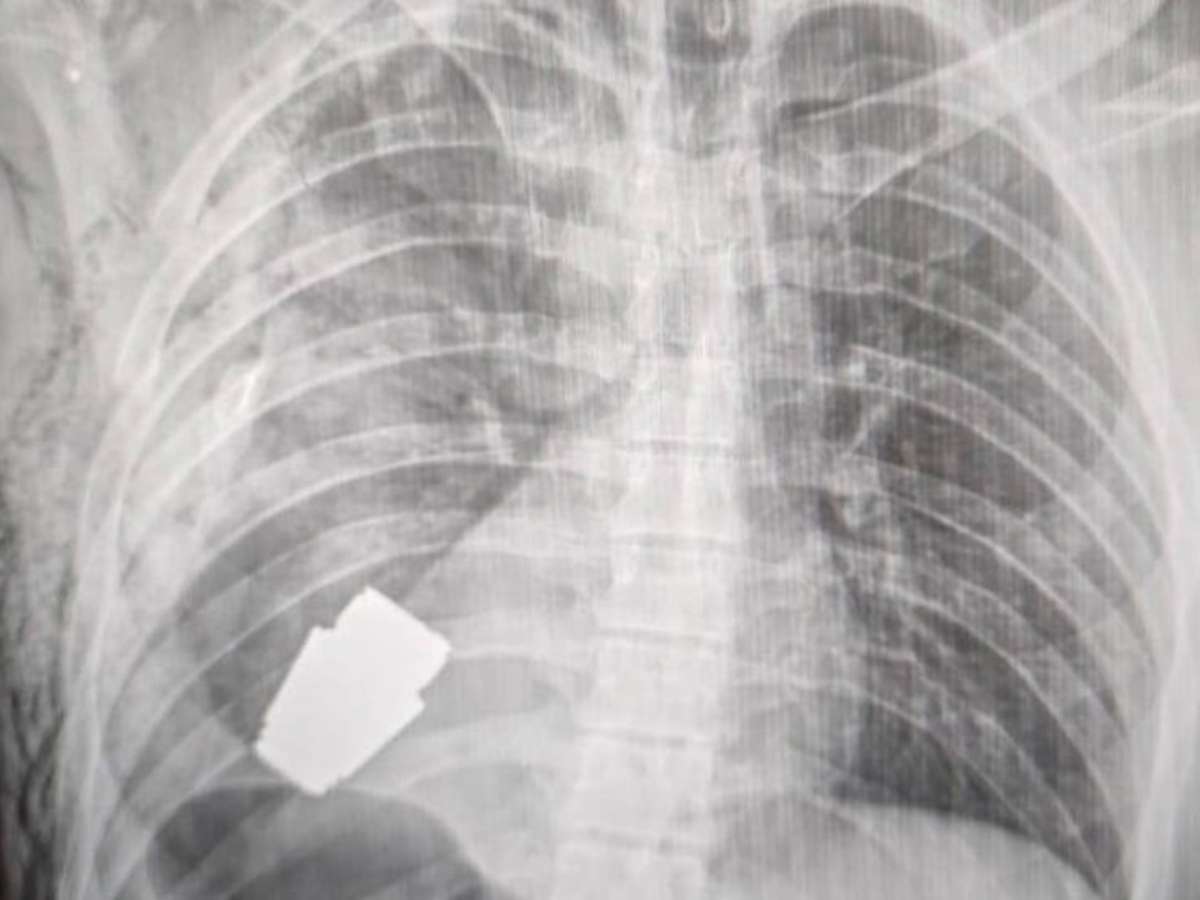

Imagem mostra raio-x da cavidade torácica com granada claramente visível

Foto: Hanna Maliar Facebook / BBC News Brasil